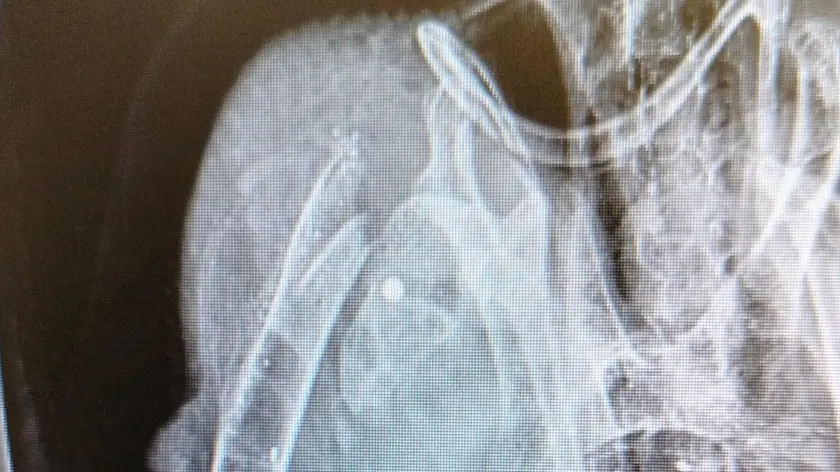

(ANSA) - PESCARA, 22 GEN - È stato operato "con successo" da Gianmaria Antonazzo nell'Ambulatorio Veterinario Vestina un giovane Ibis eremita ferito da una fucilata a Penne, nel Pescarese. L'intervento chirurgico, "delicato e difficile, ha avuto successo grazie alla tempestività e alle buone condizioni fisiche dell'esemplare recuperato a poche ore dall'abbattimento". Lo fanno sapere, in una nota, il Parco nazionale del Gran Sasso e Monti della Laga, il Comune di Penne, la Riserva naturale regionale Lago di Penne e la Cogecstre. L'ibis ferito è stato trovato in un pollaio dove probabilmente cercava il suo compagno di viaggio. Due, infatti, gli esemplari avvistati in zona nei giorni scorsi. È stato un "cittadino consapevole", ieri, a portarlo al Cras Lago di Penne, che "si è subito attivato portando il giovane esemplare in uno studio veterinario specializzato che ha subito rilevato la rottura dell'omero all'altezza della cintura scapolare e ha effettuato un delicato intervento chirurgico per tentare di restituire all'ala le migliori funzioni per permettere all'Ibis di tornare a volare". La radiografia ha confermato la "presenza di numerosi pallini da caccia nel corpo del rarissimo animale protetto". Sono stati allertati i Carabinieri forestali del Nucleo Cites, che si occuperanno delle indagini sul "folle atto di bracconaggio", cercando anche di "verificare se l'altro esemplare inseparabile Ibis, di nome 'Coccole', con l'anello numero 751, sia riuscito a sopravvivere". Il bracconaggio, sottolinea il presidente del Parco nazionale Gran Sasso e Monti della Laga, Tommaso Navarra, è "una delle minacce più gravi per la sopravvivenza della specie" e "la caccia illegale rappresenta una perdita significativa di animali reintrodotti nella natura". Per l'assessore all'Ambiente del Comune di Penne, Nunzio Campitelli, "questi atti indecenti sono un crimine contro la biodiversità", mentre "si sollecitano misure legali più efficaci per contrastare il fenomeno distruttivo contro un patrimonio naturale indisponibile dello Stato". L'ibis eremita (Geronticus eremita) abitava vaste aree dell'Europa meridionale, del Nord Africa e del Medio Oriente. Oggi sopravvive solo grazie a piccoli nuclei residui e a complessi progetti di conservazione. È in pericolo a causa di "una caccia, il bracconaggio, scellerata e inutile, e dei disturbi nei siti di nidificazione, che hanno causato un declino drammatico, portando la specie sull'orlo dell'estinzione. "Negli ultimi decenni - conclude la nota - l'Ibis eremita è diventato un emblema della biodiversità più minacciata". (ANSA).